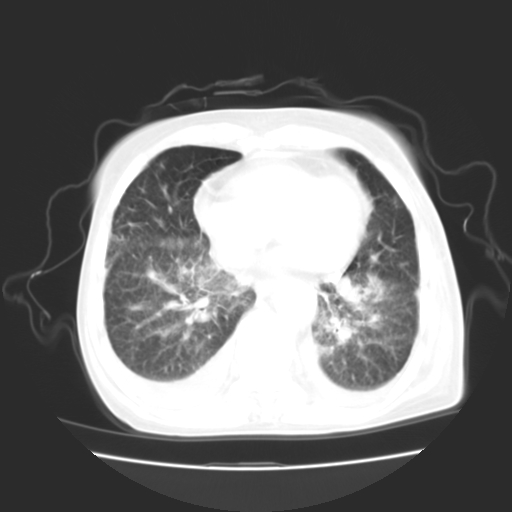

女70y乳腺ca(针吸活检)

多部位转移瘤的诊断可以肯定,我的疑问是:双肺对称高密度影及胸水是否为心衰肺水肿,病人体虚弱,不好意思图象传的乱![em9]

肺部病变为淋巴转移,肝脏转移,及局部淋巴转移。胸水可能为淋巴回流受阻(血性的考虑胸膜转移)

癌性淋巴管炎,肝脏转移,瓷胆囊

1)左侧乳腺癌并左侧腋窝及纵隔淋巴结转移,两肺淋巴道转移(癌性淋巴管炎),肝脏多发性转移。2)双侧胸腔积液。3)慢性胆囊炎。

3、双肺癌性淋巴管炎;

1)左侧乳腺癌并左侧腋窝及纵隔淋巴结转移,肝脏多发性转移。2)双侧胸腔积液伴双肺蝶翼样磨玻璃高密度影,双侧肺门血管影增粗(图像不全,肺门层面没纵隔窗),考虑心功能不全所致。3)慢性胆囊炎伴壁钙化。